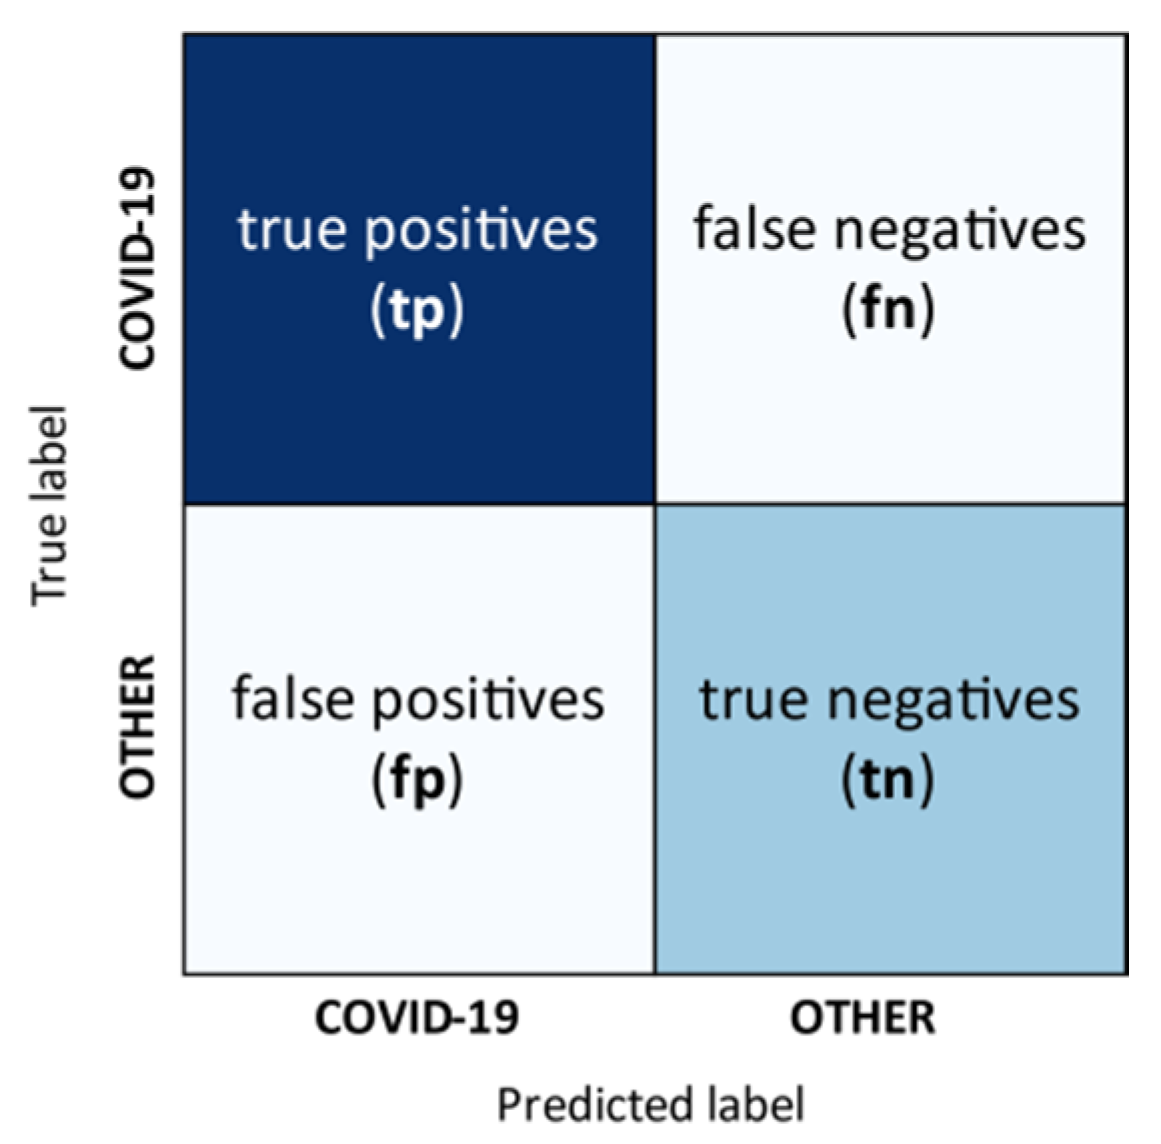

3.6. Performance Measures

- true positives (tp)

- true negatives (tn)

- false positives (fp), and

- false negatives (fn).